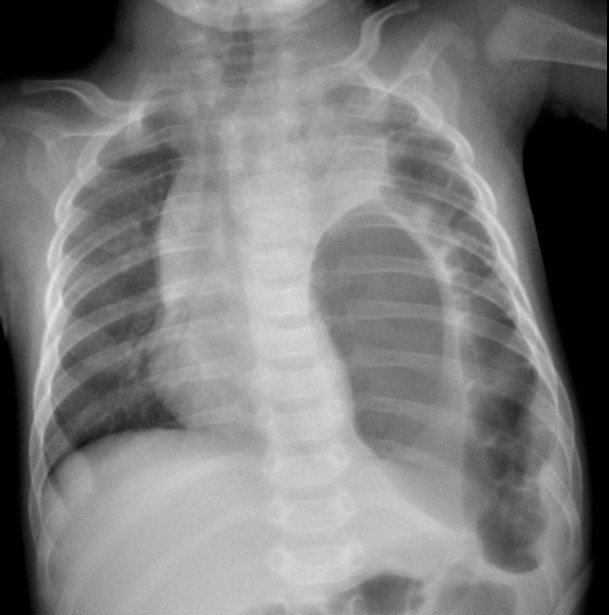

N. di 4 mesi � giunto alla nostra osservazione presso l'ambulatorio di pediatria generale perch� la madre da qualche ora aveva la sensazione che il piccolo respirasse male. Inoltre riferiva che il piccolo appariva addormentato, che si era alimentato meno del solito negli ultimi 2 pasti (assumeva LMS integrato con latte di formula) e che aveva presentato un conato di vomito seguito da transitorio ipotono. Dall'anamnesi ostetrico-ginecologica non emergevano elementi degni di nota. Era apiretico e presentava colorito roseo. Appariva tuttavia scarsamente reattivo e soporoso. L'obiettivit� polmonare mostrava tachipnea (FR 90 atti/min) con lievi rientramenti sottocostali, silenzio respiratorio a sinistra senza rumori patologici aggiunti, mentre a destra il MV era normotrasmesso, SatO2 96-97%. Le restanti obiettivit� clinica generale e neurologica apparivano nella norma. Considerato il quadro clinico, nel sospetto di un esteso focolaio bronco-pneumonico, il paziente � stato inviato urgentemente presso l'ambulatorio pediatrico di libero accesso dell'Ospedale di Parma, dove si � deciso di ricoverare il piccolo. Gli esami ematochimici eseguiti all'ingresso evidenziavano leucocitosi neutrofila (GB 25.190/Ul, N 67%), iperglicemia (glucosio 155 mg/dl), negativit� della PCR (0,15 mg/l) e normalit� dell'emogasanalisi arteriosa. La radiografia del torace ha mostrato erniazione dello stomaco e di buona parte del colon sinistro nell'emitorace sinistro con atelettasia pressoch� completa del polmone omolaterale, deviazione controlaterale del mediastino, normalit� del polmone destro (Figura). Dopo il riscontro dell'ernia diaframmatica congenita, a completamento diagnostico � stato eseguito un esame ecocardiografico che ha evidenziato assenza di flusso nell'arteria polmonare sinistra. Il giorno seguente al ricovero il piccolo � stato trasferito presso la Chirurgia Pediatrica dove � stato sottoposto a intervento di correzione dell'ernia (nel corso della procedura � stata riscontrata anche la milza nel torace di sinistra). Il decorso post-operatorio � stato ottimo: il piccolo ha ripreso precocemente ad alimentarsi per via enterale, era gi� canalizzato in seconda giornata, il polmone sinistro si � completamente riespanso come mostrato dall'Rx torace di controllo che appariva nella norma (eseguito il giorno dopo l'intervento). Attualmente N. si alimenta e cresce bene, non presenta nessun problema respiratorio n� gastrointestinale.

Figura Un distress respiratorio da ernia diaframmatica Per ernia diaframmatica si intende una comunicazione anomala tra le cavit� addominale e toracica, associata o meno a presenza del contenuto addominale nel torace. L'eziologia pu� essere congenita o traumatica. Si distinguono le ernie postero-laterali: la sinistra (o di Bochdalek, 80% dei casi) e la destra (20% dei casi), le retrocondrosternali (di Morgagni-Larrey, 2% di tutte le ernie diaframmatiche congenite), le iatali (a livello dello iato esofageo) e le paraesofagee (adiacenti allo iato). Quando si parla di ernia diaframmatica congenita (CDH) in genere ci si riferisce alla variante di Bochdalek. Sebbene la CDH sia caratterizzata da un difetto diaframmatico strutturale, uno dei principali fattori limitanti per la sopravvivenza � l'ipoplasia polmonare associata. Infatti la presenza dei visceri/organi in cavit� toracica pu� causare una compressione costante sui polmoni fetali in via di sviluppo, determinando un vario grado di ipoplasia polmonare (omo- e controlaterale) anche se in genere pi� grave dal lato dell'ernia. L'ipoplasia � caratterizzata da riduzione delle diramazioni bronchiali e dello sviluppo alveolare e arteriolare (che clinicamente produce ipertensione polmonare). L'incidenza � stimata da 1:2000 a 1:5000 nati vivi, M:F = 1:2. I visceri/organi pi� frequentemente erniati sono lo stomaco e l'ileo, il lobo sinistro del fegato e la milza. In circa un terzo dei casi sono associati lesioni del sistema nervoso centrale, malformazioni cardiache, atresia esofagea, palatoschisi, trisomia dei cromosomi 21, 13, 18. Generalmente la CDH si rende evidente nelle prime 24 ore di vita con segni di distress respiratorio acuto (tachipnea, cianosi, gasping, retrazioni inspiratorie e sforzi respiratori) progressivamente ingravescenti parallelamente alla distensione intestinale, che determina un peggioramento della compressione parenchimale polmonare e della dinamica ventilatoria.